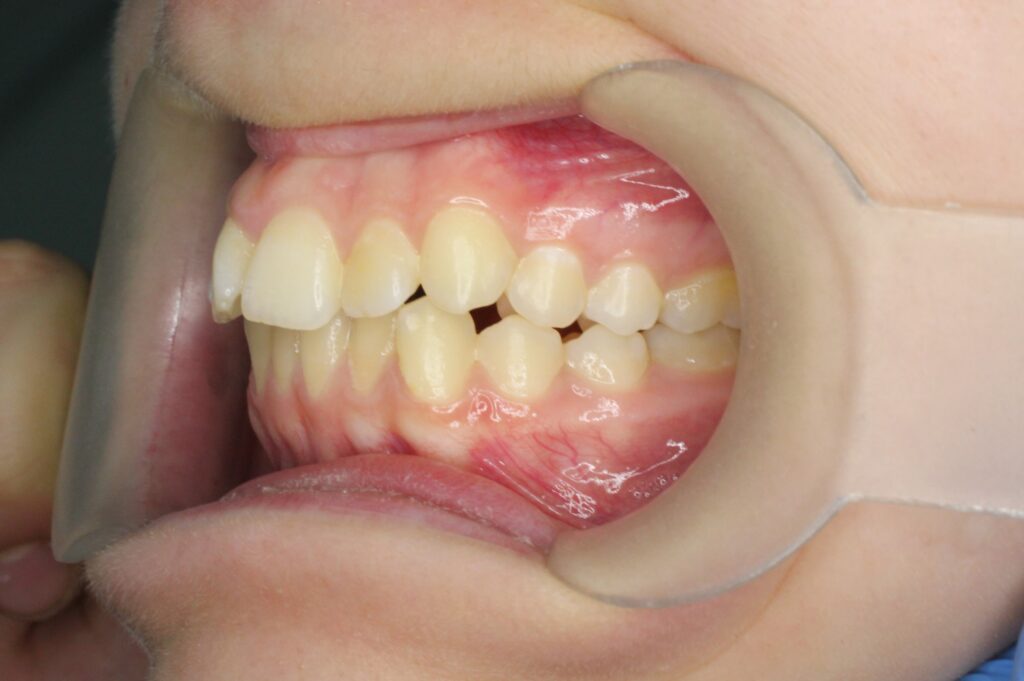

Ситуация до лечения

Жалобы: Пациентка обратилась с жалобами на неровное положение передних зубов.

Диагноз: дистальный прикус, сужение верхнего и нижнего зубных рядов, скученность фронтальной группы зубов на верхней и нижней челюсти.

пациент до лечения брекетами